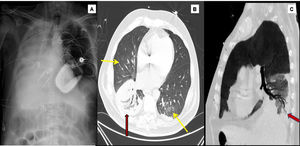

1A) Chest X-ray. Subtotal atelectasis of the right lung, ECMO ejection cannula in the right jugular and suction cannula in the inferior vena cava. Contrast computed tomography (arterial phase, lung window). 1B) Predominantly central ground glass infiltrates (yellow arrows) observed in both lung fields. Consolidation in right lower lobe (red arrow). 1C) Permeability of the bronchial tree observed in the center of the consolidation focus (For interpretation of the references to colour in this figure legend, the reader is referred to the web version of this article).

However, his subsequent course was marked by respiratory worsening with alveolar opacities on the right lung base, fever, and raised acute phase reactants despite favorable hemodynamic, echocardiographic and NTproBNP values. Although microbiological results were not yet available, these data, together with a favorable response to wide spectrum empirical antibiotics, supported the suspicion of right lower lobe pneumonia associated with mechanical ventilation. The infectious disease was beginning to resolve, but then, on day 7 of admission, the patient developed a sudden desaturation of up to 85% despite increasing FiO2 to 100%. Auscultation revealed disseminated rhonchi with marked hypoventilation of the right hemithorax, and blood clots were aspirated through the orotracheal tube. An urgent bedside chest X-ray showed atelectasis of the right lower lobe with bilateral alveolar opacities in the rest of the parenchyma. The patient presented rapidly progressing hypoxemia within the next few minutes (minimum PaO2 32 mmHg) that did not improve with right lateral decubitus Ambu ventilation, along with hypotension and hyperlactacidemia (lactate 5.1 mmol/L) refractory to the administration of increasing doses of volume expanders and vasopressors. Given the immediate risk to life, we decided not to perform fiberoptic bronchoscopy and ruled out the option of selective orotracheal intubation. We therefore prioritized respiratory and circulatory stabilization, using ultrasound guided cannulation to establish venovenous ECMO at the bedside within a few minutes, without sodium heparin, by placing a 23 F afferent cannula via the right femoral vein and a 17 F efferent cannula via the right jugular artery. This procedure left us with the option of subsequently adding an arterial cannula for hemodynamic support in the form of venoarterial ECMO if necessary. Oxygenation was immediately normalized after implantation, and hemodynamics improved gradually. We could then proceed with diagnostic fiberoptic bronchoscopy that showed the presence of fresh blood in the left bronchial tree and hyperemic mucosa with no underlying injury after aspiration, and a cast of thrombotic material in the right pulmonary tree that was impossible to extract completely. Fig. 1 shows the chest X-ray after ECMO cannulation confirming an sufficient distance between the cannulas to prevent recirculation phenomena, the disappearance of left hemitorax condensations, and persistent right pulmonary atelectasis where the presence of a clot in the bronchial lumen within a few centimeters of the carina is observed.

Support was maintained with ECMO at a flow of 4 L/min and FiO2 for PaO2 > 60 mmHg, under protective ventilation, without anticoagulation. Daily bronchoscopies were performed until the thrombotic material was extracted in its entirety. After 4 days on ECMO, reexpansion of the right lung was achieved with no new bronchial bleeds. Tests to disconnect venovenous ECMO were then undertaken and the patient was subsequently decannulated. This was followed by a computed tomography scan with contrast in the arterial and venous phases that detected an image of right basal condensation with no evidence of bleed foci in the bronchial circulation, fistulas, cavitations or other lesions (fig. 2). Hemoptysis was eventually attributed to bleeding associated with pneumonia in a patient with pulmonary hypertension receiving anticoagulation. Progress in the following weeks was gradual, and the patient was discharged 69 days after admission.